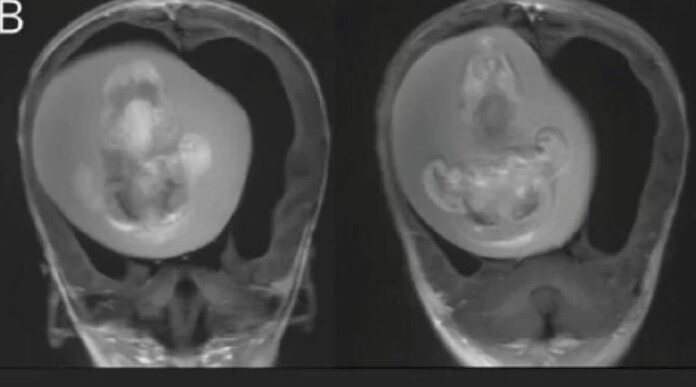

Imagens de tomografias computadorizadas mostraram que o feto, de aproximadamente 10 centímetros de comprimento, tinha desenvolvido os membros superiores, ossos e unhas, o que sugere que ele cresceu por alguns meses enquanto ainda estava no útero da mãe.

Feto de 10 centímetros de comprimento tinha desenvolvido os membros superiores, ossos e unhasHuashan Hospital/ Divulgação

Imagem de tomografia mostra feto desenvolvido no cérebro de irmã gêmea Huashan Hospital/ Divulgação